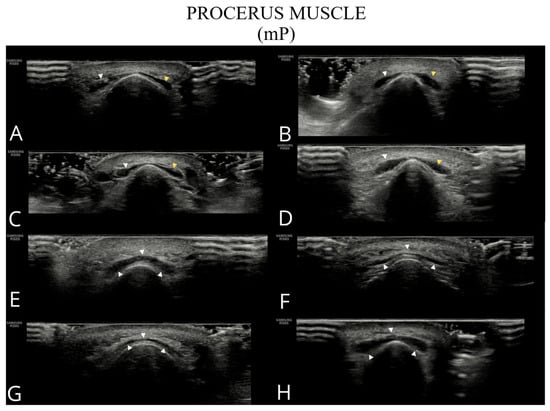

- Procerus (mP): The transducer was positioned transversely over the nasal bone, the measurement was taken at half the muscle length.